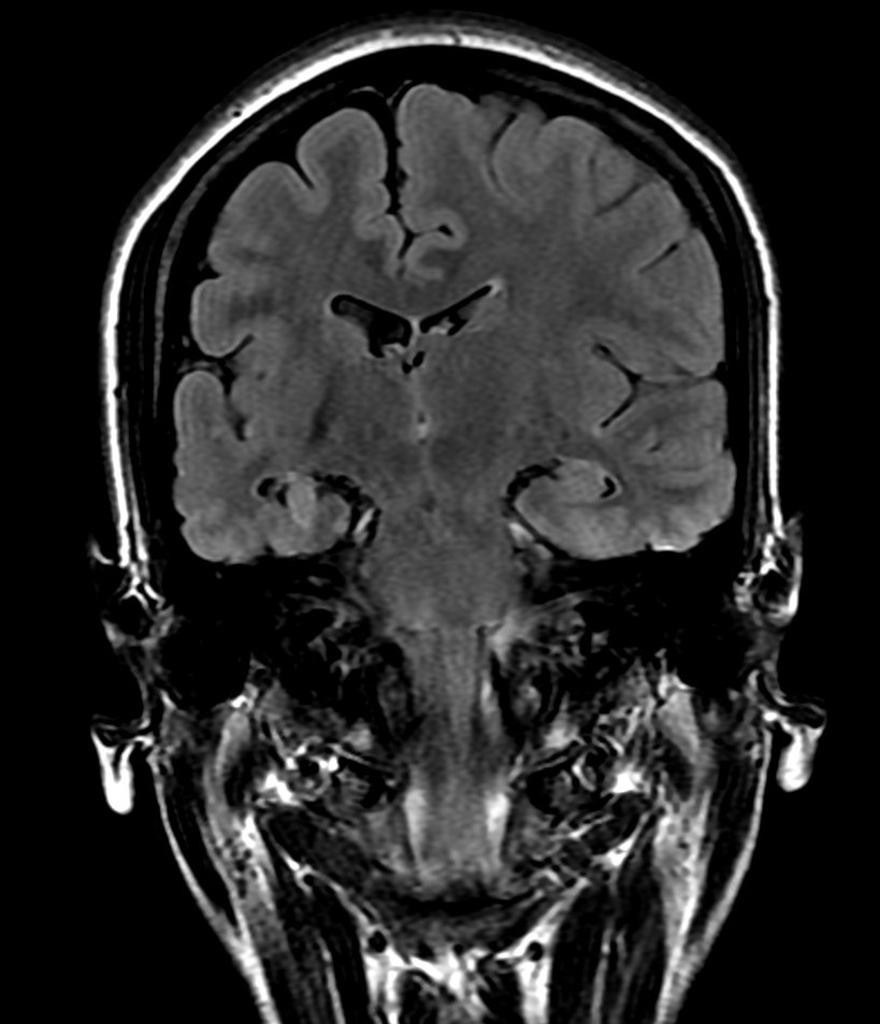

DYSPLASIE CORTICALE FOCALE

• Mieux visible à 3 Tesla, à opérer

• Malformation avec cortex anormal en position anormale

• 2ème cause d’épilepsie pharmaco-résistante chez l’adulte

• FRONTALE et CENTRALE (sillons frontaux sup et inf)

• Frontale > centrale > parietale > occ > temp

• 1/3 IRM négative (30%)

• Elargissement focal du ruban cortical en T1

• Flou du contour SB/SG : « blurring »

• +/- HS cortex et SB adjacente

• Bande en HS FLAIR rejoignant VL : « transmental sign »